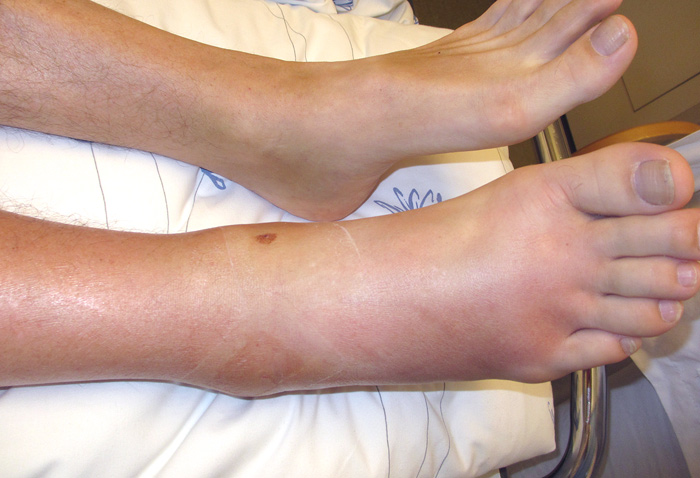

En norsk mann i 60-årene ble innlagt i medisinsk avdeling på grunn av sterke smerter i høyre ankel. Smertene var ledsaget av intermitterende feber over 39 °C. Han var tidligere stort sett frisk, bortsett fra at han var innlagt med malaria i 2011. Pasienten brukte Albyl-E 75 mg 1 · 1 som fast medikasjon som primærprofylakse mot hjertesykdom. Han kom hjem til Norge fra et utenlandsopphold fem dager i forveien. Under reisen og to uker før innleggelsen hadde han merket forbigående nesetetthet og ubehag i svelg. Ved innleggelsen hadde han tiltagende smerter fra høyre ankel. Han hadde tråkket over og forstuet ankelen en måned i forveien, men det var ingen større traumer i historien. Han oppga også generelle smerter i skuldre, rygg og venstre hofte. Pasienten var ved ankomst til sykehuset høyfebril med temperatur 39 °C, normalt blodtrykk (119/65), og puls var 86, regelmessig. Det var normale auskultasjonsfunn over hjerte og lunger. Han hadde diffus rubor både på medialsiden og lateralsiden av høyre ankel, samt varmeøkning og petekkialt utslett over ankelleddet (fig 1).